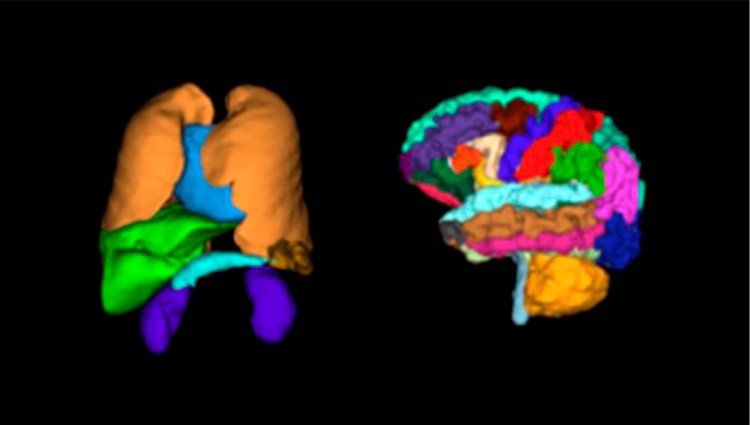

- Mejora de imagen

- Segmentación de la anatomía

- Detección / Diagnóstico

- Soporte de flujo de trabajo